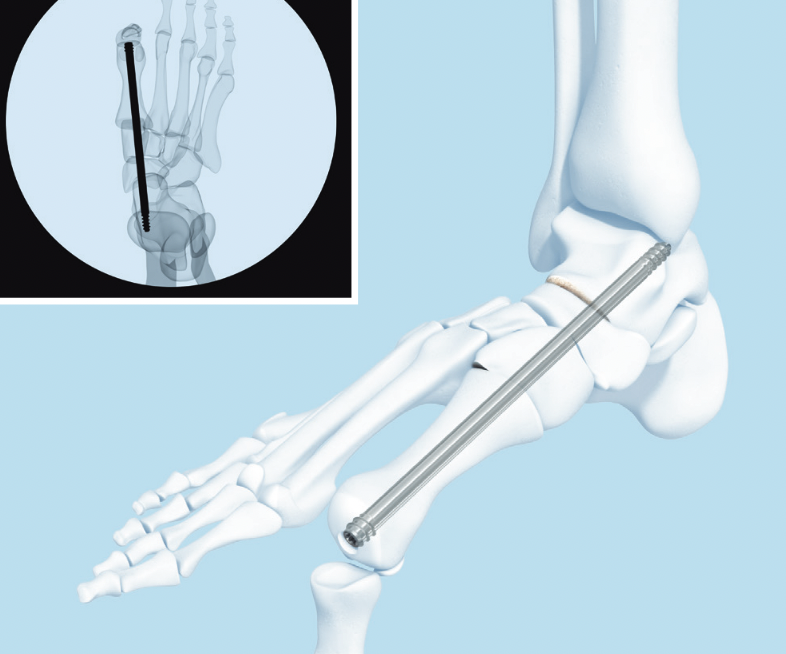

- intramedullary beams

- axial screw fixation from 1st MTPJ through metatarsal into talus

- also IM screw through 2nd and 3rd metatarsal into talus

Synthes Midfoot Fusion Bolt surgical technique PDF